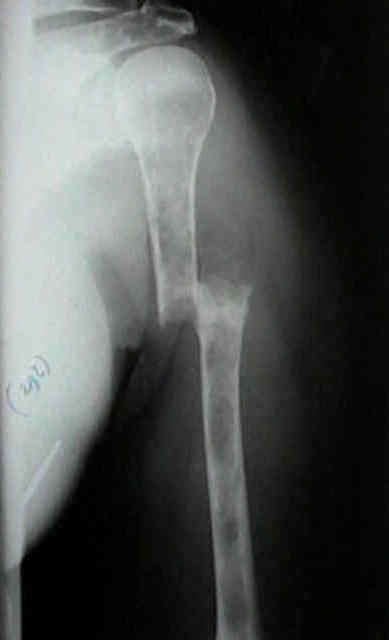

Radiographic Studies

• standard x-rays may show diffuse osteopenia

• "punched-out lesions" w/ no surrounding new-bone formation;

• over time lesions may change from diffuse osteopenia to more permeative moth-eaten destructive pattern, sometimes w/ cortical expansion;

• bone destruction occurs w/ little or no reactive bone formation unless pathologic frx is present;

Humerus 12